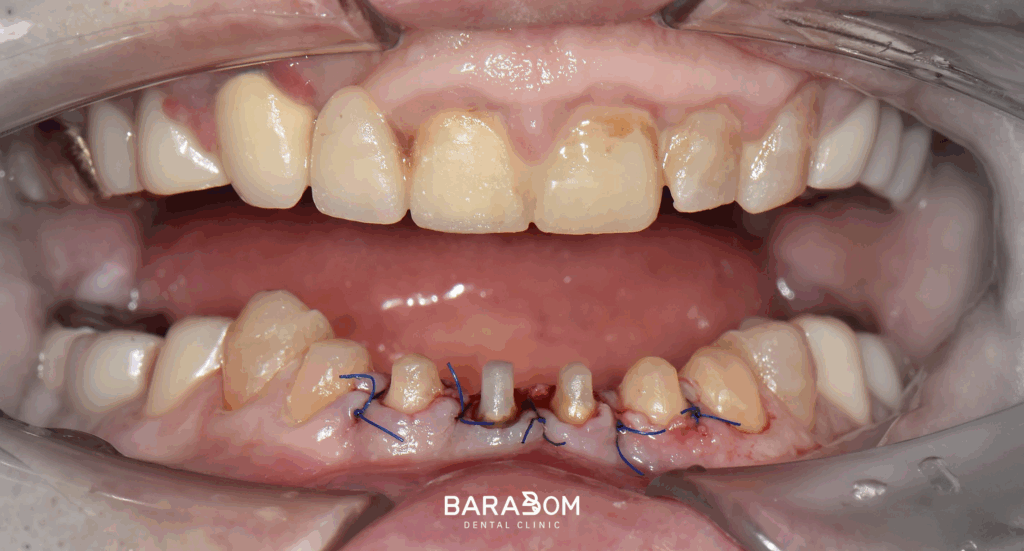

준비한 사진을 보시면, 윗니가 아랫니를 일절 다 덮을 정도로 깊게 물리고 있습니다.

더불어 교합력이 센 탓에 교모가 꽤 심하게 진행되었습니다.

이런 경우, 제가 준비한 케이스처럼 수직 고경이 상실될 수 있습니다.

대개 교모로 인하여 수직 고경이 상실된 케이스를 보면 치관의 길이가 매우 짧습니다. 이런 상태에서 크라운을 씌우게 되면 당연히 안정을 얻기 어렵습니다.

그럼 자주 보철이 탈락하게 되어 불편으로 이어질 수 밖에 없는데, 현재 하악 앞니 뿐만 아니라 어금니도 치아 머리의 길이가 짧은 상태였습니다. 하악 절치부 치관 길이가 매우 짧으며, 상악 절치 구개부와 간격이 불과 2mm 이내였습니다. 현재 상태로써 새로운 보철을 제작하긴 어렵다 판단되고 있습니다.

앞서 설명드린 것처럼 교합고경을 재건할 때, 여러 사항을 고려하여 신중을 기여해야 됩니다. 하악 구치부 크라운 수복을 진행한 결과, 앞니쪽에 3mm 가량의 공간이 형성되었습니다.

보철이 올라갈 여유가 확보되긴 했으나 그 정도가 충분한 건 아니라 골 삭제를 동반한 치관연장술을 함께 진행하는 방향을 택해볼 수 있습니다. 말 그대로 잇몸뼈를 어느 정도 삭제해줌으로써 치아 머리의 길이를 늘려주는 술식을 말합니다.

전/후 사진을 보시면 확실히 앞니의 치아 머리 부분이 연장되면서 크라운이 올라갈 공간이 확보된 모습이 관찰되고 있습니다.